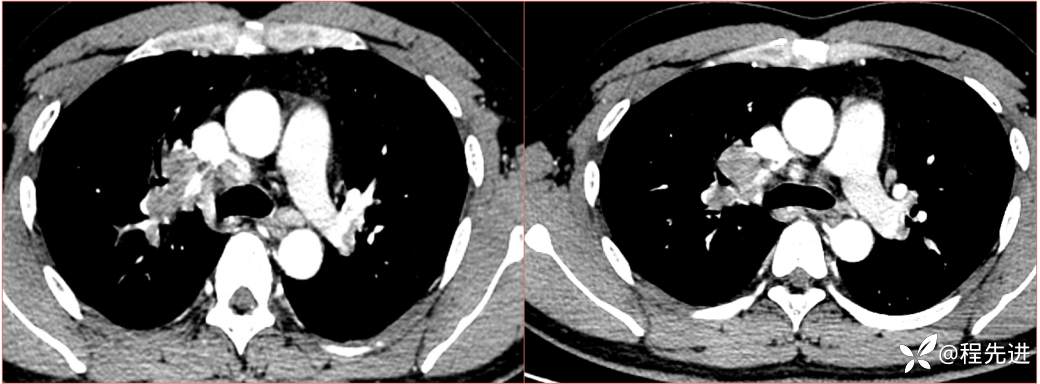

2023国庆特别精彩病例(一)|阵发性刺激性咳嗽,咳少量白色粘液痰1周|结果已公布

患者年龄:34岁

简要病史:患者一周前无明显诱因出现阵发性刺激性咳嗽,咳少量白色粘液痰,咳嗽无明显昼夜节律性,无发热、畏冷、寒战,无头痛、胸闷、胸痛,自行服药后 (具体不详) 症状无缓解,3天前外院胸片检查示右上病变

辅助检查:肺肿瘤标志物:神经元特异性烯醇化酶(NSE):35.72ng/ml(参考值0-16.3);非小细胞肺癌相关抗原211、胚抗原糖类抗原125、铁蛋白、鳞状细胞癌抗原未见异常